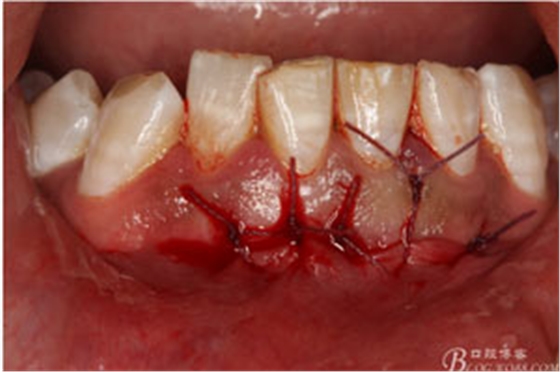

圖17.縫合

術(shù)后局部冷敷一日,靜脈滴注抗生素三日。同時注意口腔衛(wèi)生。